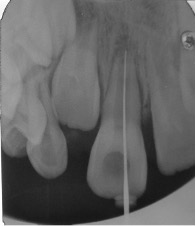

La secuencia de tratamiento se realizó en 2 sesiones: la primera sesión se basó en la desinfección del conducto radicular, utilizando como agente irrigante inicial 20ml de hipoclorito de sodio al 2,5% y 10ml clorhexidina al 2%, como irrigante final, intercalando la irrigación con 10 ml de cloruro de sodio, para evitar la formación de precipitados;2,5,15,18,19 luego el conducto radicular fue secado con conos de papel estériles. Finalmente, en el conducto radicular se colocó la pasta antibiótica 3Mix (Figura 3-5), mezclado previamente según las indicaciones de Quintana y cols.22 La segunda sesión, se realizó a las 2 semanas,22 lográndose la inducción del sangrado (formación del andamio) y colocándose una barrera cervical de MTA. El éxito del tratamiento de revascularización pulpar también depende en gran parte de una adecuada reconstrucción y sellado a nivel coronal, en este caso se realizó utilizando materiales ionoméricos y resinosos (Figura 6-10).

Figura 4: Preparación biomecánica con lima K N°35, en una longitud de 12 mm. Sólo a nivel cervical para mejorar visibilidad y el acceso al conducto radicular. Irrigación inicial con hipoclorito de sodio al 2.5% y 10ml clorhexidina al 2%, como irrigante final, intercalando la irrigación con 10ml de cloruro de sodio.

Figura 5: Aplicación de Pasta 3 Mix intra conducto con lima K No 25. El sellado de la entrada del conducto radicular se realizó con pasta de eugenato + ionómero de vidrio por un período de 15 días. Control radiográfico.